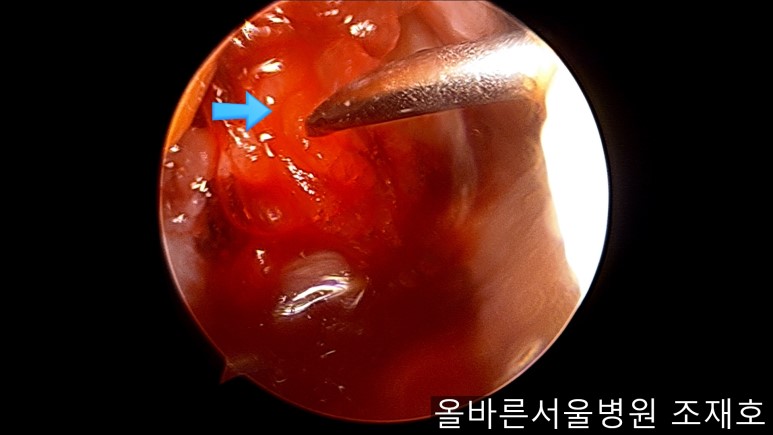

通过关节镜图像可看到:由于内侧股骨髁软骨损伤骨头已经显露出来。

胫骨上端的软骨损伤严重,也露出了骨头。

前方十字韧带处没有覆盖滑膜的粘液样变性的外观及稳定性无异常。

与内侧对照,外侧的软骨及软骨板无损伤。

用水冲洗清理空间,为注入CARTISTEM做准备。

以注射的方式将CARTISTEM填满每一个孔。

填充完每个孔后将剩余的CARTISTEM涂抹在孔上方。